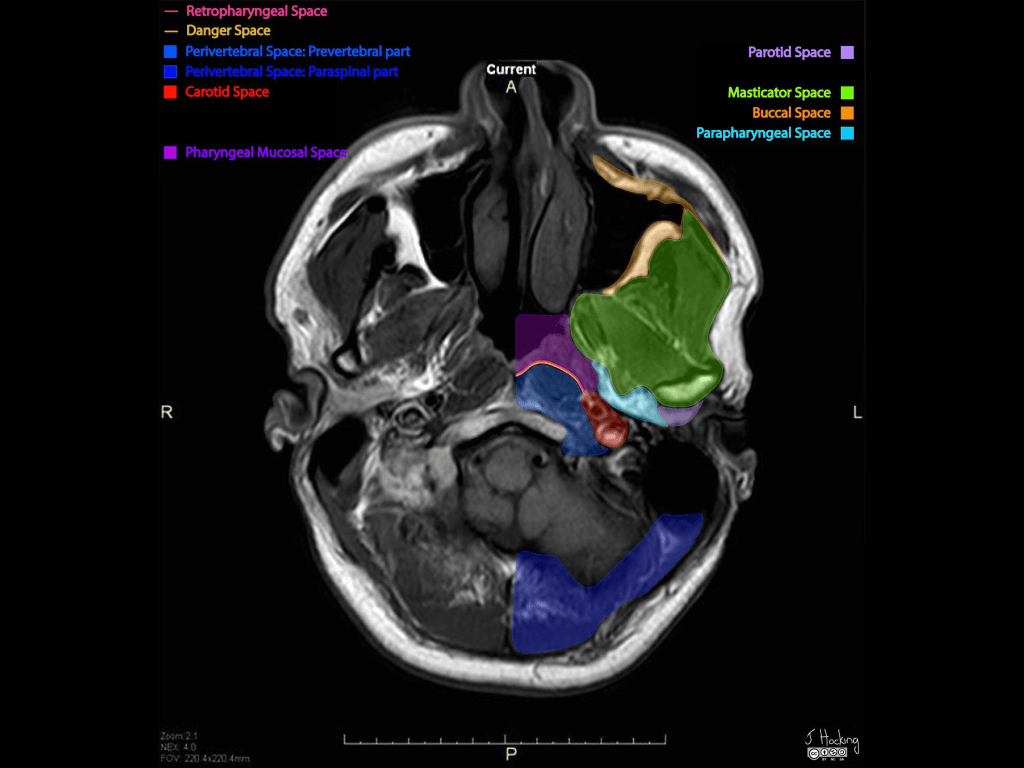

- Boundaries and relations:

- Anteriorly:

- The buccal space

- Posterolaterally:

- Parotid space

- Medially:

- Parapharyngeal space